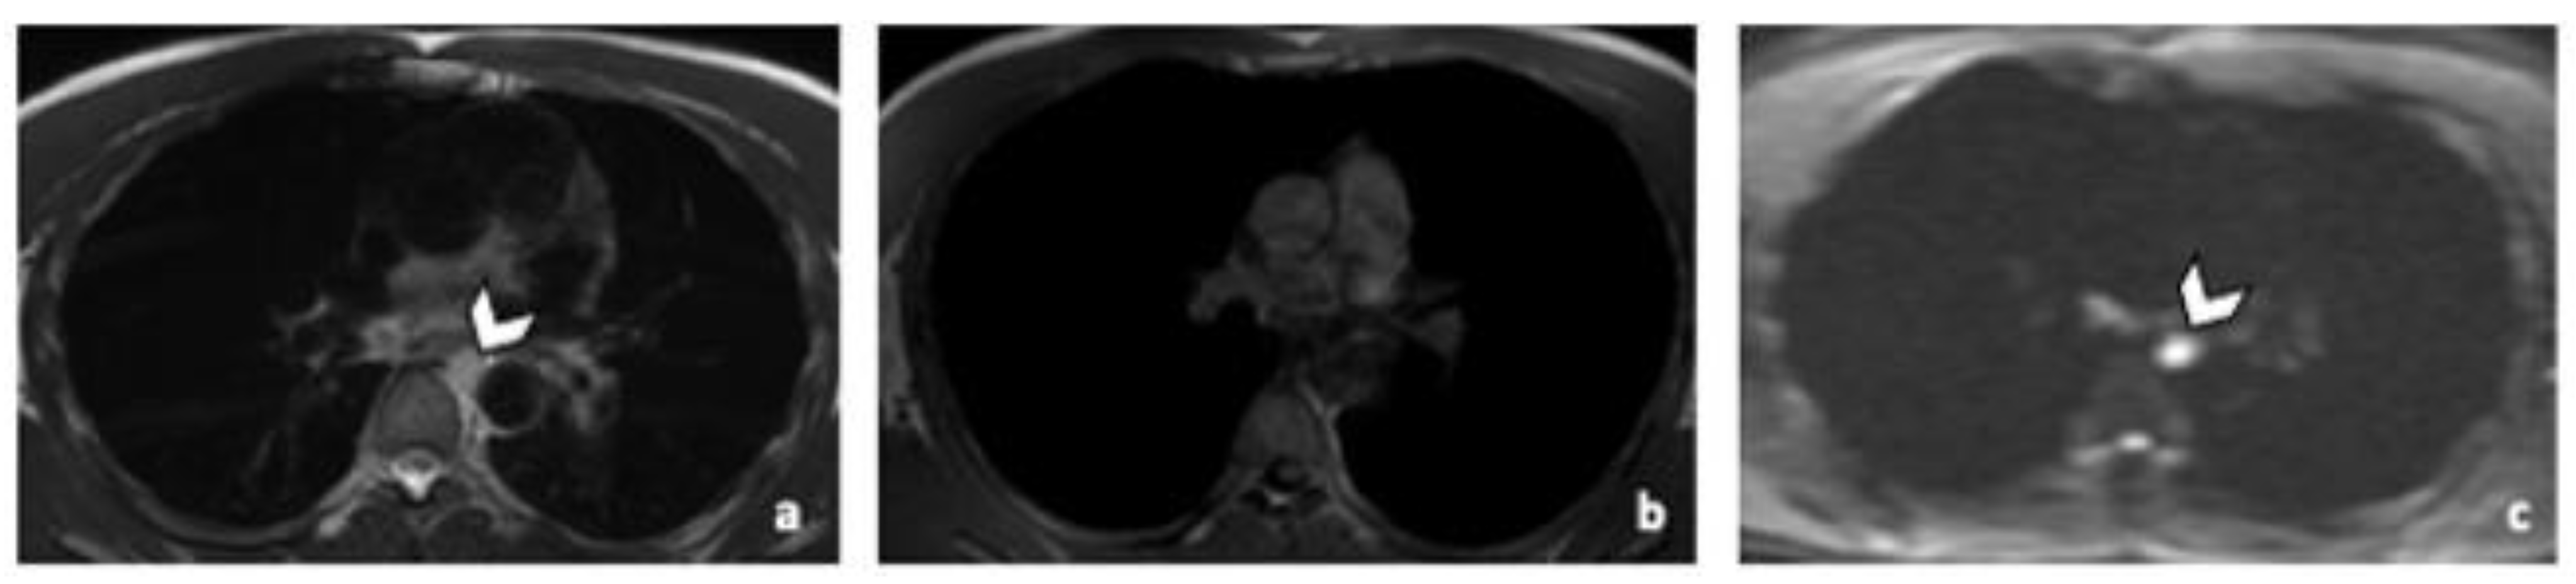

3.3.2. DLN Metastases